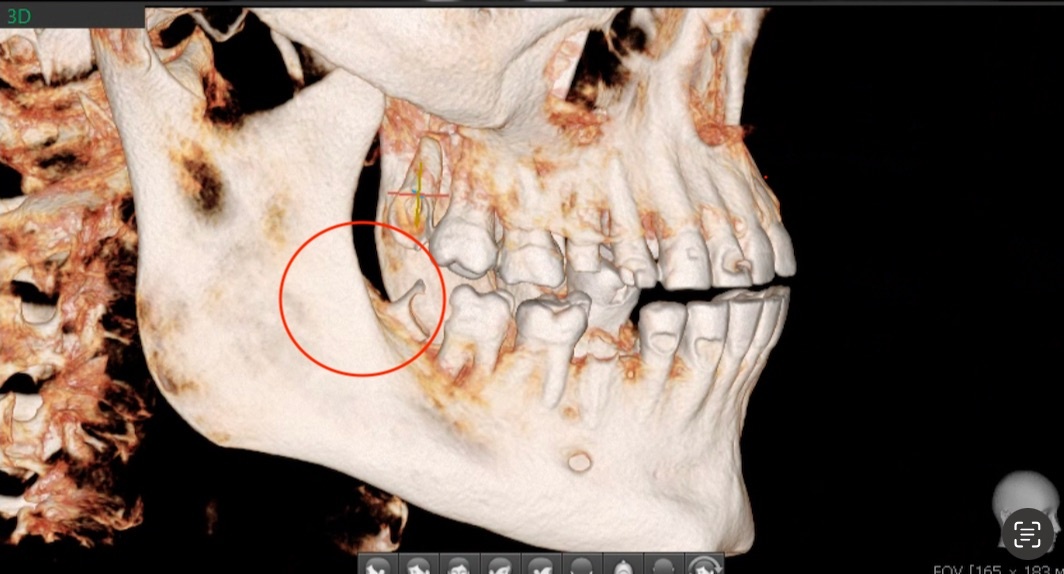

На верхней челюсти кость за восьмёркой ограничена в длину, бугор верхней челюсти с сохранным 8 зубом, зачастую, очень мелкий или его нет вовсе. Перемещать зуб в пустоту невозможно.

Даже если зуб прорезался, кости не будет у большинства (почти абсолютного). Удаляем 8, получаем (или не получем, от генетики зависти) самый ценный костный материал, пригодный для трансплантации